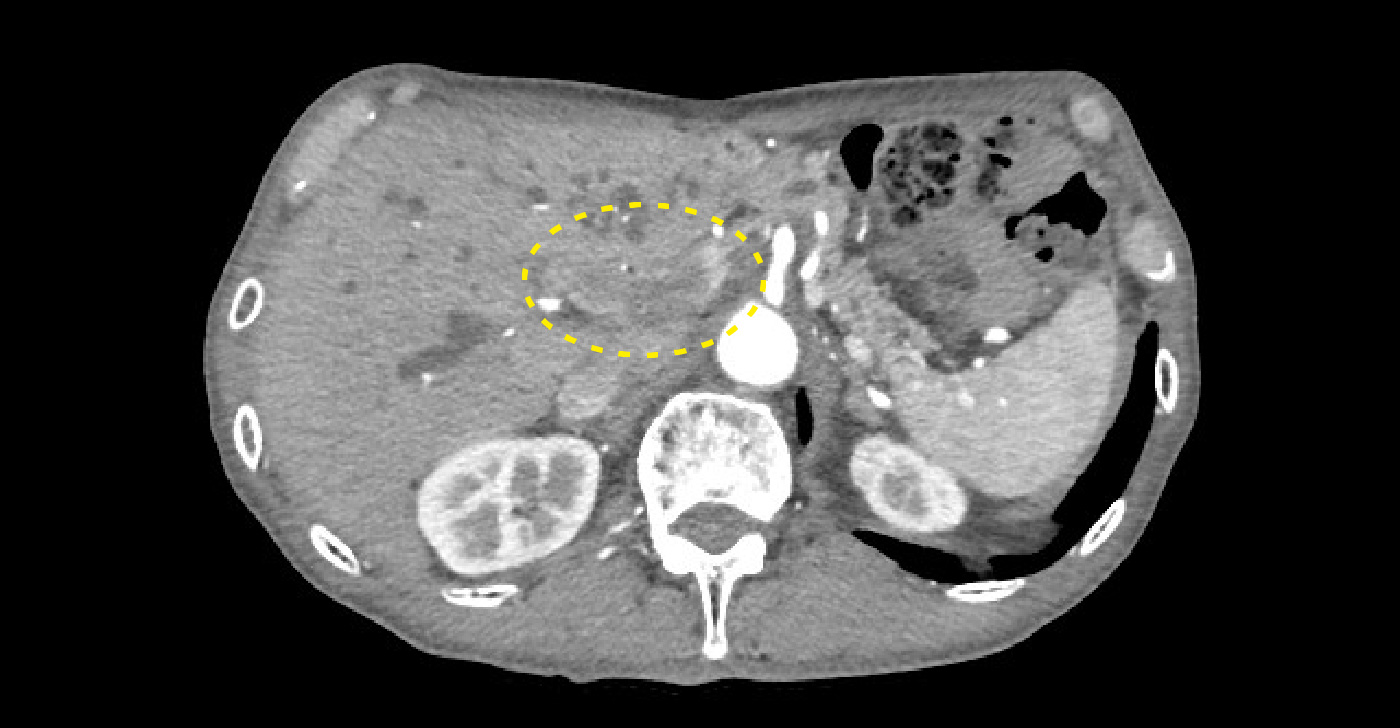

造影CT動脈相/造影CT動脈相*水平断|胆嚢底部に造影効果を伴う腫瘤と膵鉤部~下大静脈周囲リンパ節が一塊となって腫脹

造影CT動脈相/造影CT動脈相*水平断

胆嚢底部に造影効果を伴う腫瘤と膵鉤部~下大静脈周囲リンパ節が一塊となって腫脹